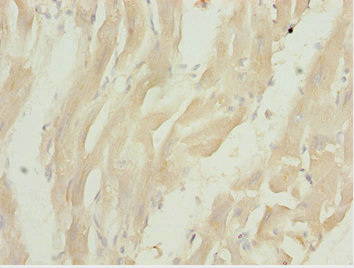

Immunohistochemistry of paraffin-embedded human heart tissue using CSB-PA836674ESR1HU at dilution of 1:100